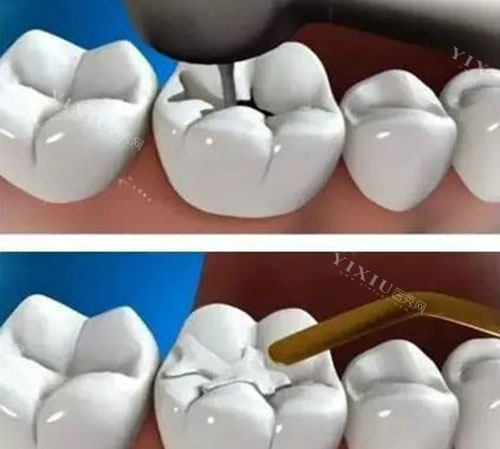

在选择补牙材料的时候,王医生给我介绍了几种不同的材料,有树脂的、玻璃材料的,还跟我讲了每种材料的优缺点。他没有一个劲儿地推荐贵的材料,而是根据我的牙齿情况和需求,建议我选择了一款性价比比较高的树脂材料。这种贴心的服务真的让我特别感动。

开始补牙了,我心里还是有点紧张的。王医生一直在旁边安慰我,让我放松。整个补牙过程中,他的动作特别轻柔,时不时还会问我有没有不舒服。说实话,我原本以为补牙会很疼,但是在王医生的操作下,我并没有感觉到太多的疼痛,只是偶尔有一点点酸胀的感觉。

补完牙之后,王医生又给我讲了很多注意事项,比如短期内不要吃太硬、太黏的东西,要注意口腔卫生等等。我按照他说的做,牙齿也没有出现什么问题。现在已经过去一段时间了,补过的牙齿就跟自己原来的牙齿一样,吃东西也不疼了,我真的特别满意。